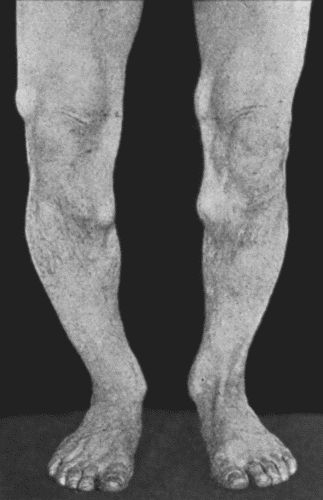

163.Charcot's Disease of Left Knee 534

164.Charcot's Disease of both Ankles: front view 535

165.Charcot's Disease of both Ankles: back view 536